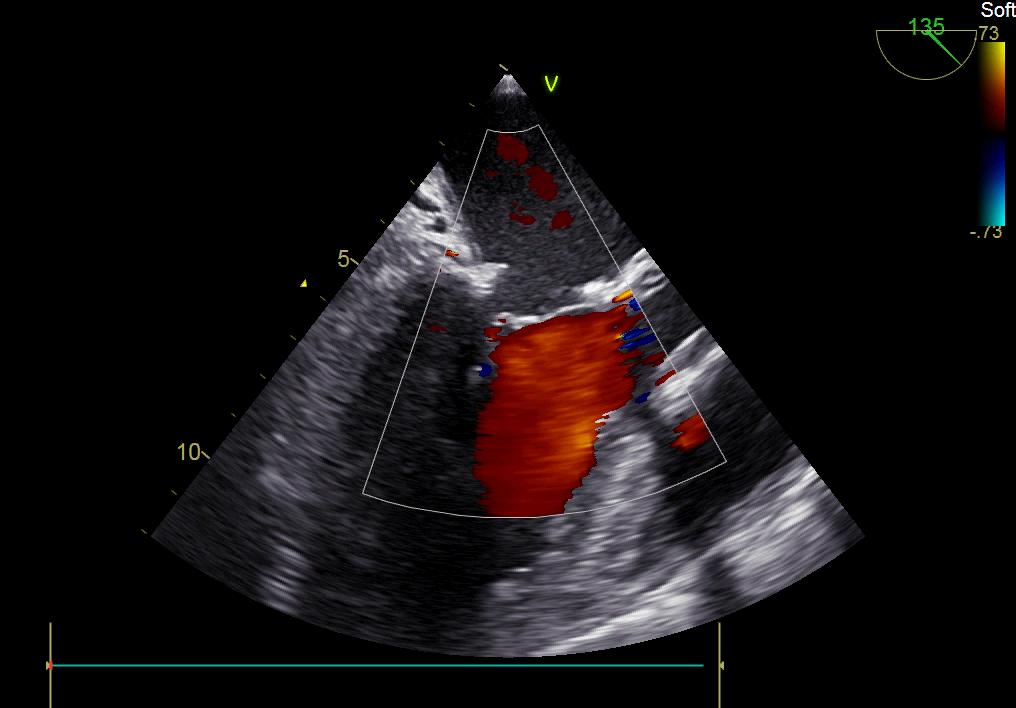

術后彩超